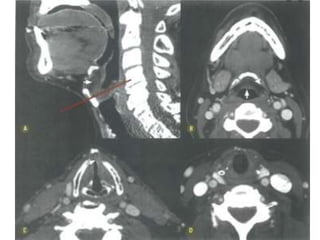

Laringe

 Achados clínicos

 Rouquidão

 Tosse crõnica, dispneia, disfagia.

 CEC: 95-98%

 60% na glote

 30-40% supraglote

 <5% subglote

 Tabagismo e etilismo

Laringe  Achados clínicos Rouquidão  Tosse crõnica, dispneia, disfagia.  CEC: 95-98%  60% na glote  30-40% supraglote  <5% subglote  Tabagismo e etilismo